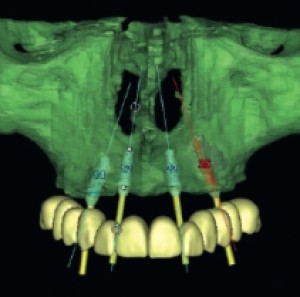

Obiettivi: Proporre una nuova tecnica per la riabilitazione di edentulie parziali o totali a livello del mascellare superiore.Materiali e metodi: Viene descritta la possibilità di estendere le...

O33Implantologia 03 Dicembre 2012

Obiettivi: Scopo dell'articolo è la descrizione di una metodica per la funzionalizzazione immediata dei settori posteriori o dell'intera arcata mascellare tramite impianti assiali e inclinati...